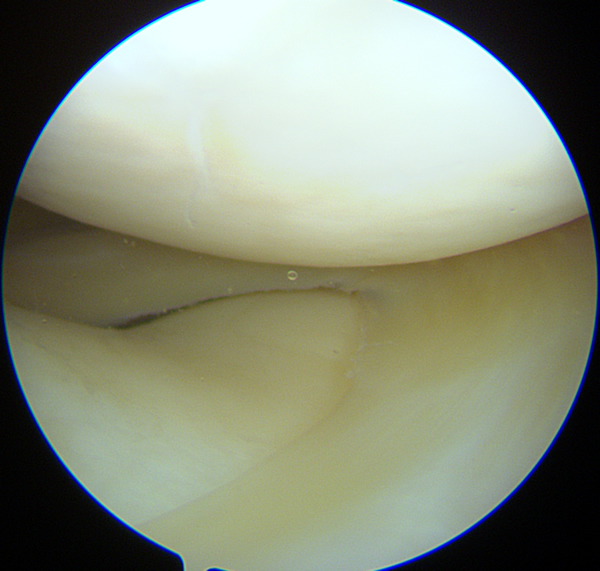

Menisque normal, sous arthroscopie.

Sous arthroscopie, image d'une fissure dégénérative du ménisque qui est "feuilleté". Notez que parallèlement, le cartilage est parfait, comme neuf.